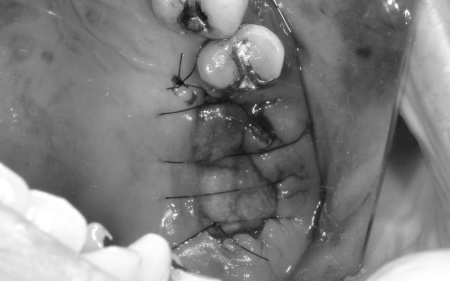

左上については、顎の骨が大きく失われているため、骨を再生させる処置「GBR(骨再生誘導法)」を実施してインプラントを支えるために必要な骨量を確保したうえで、インプラントを埋入する計画を立てました。

まずは左上奥歯2本を抜き、骨が足りない部分に骨補填剤を入れ骨の再生を促します。

経過観察後、十分な骨量を確保できたことを確認し、インプラントを埋入しました。

次に、右下に装着されているブリッジを除去してから右下の親知らずを抜き、欠損部(第1大臼歯、第2大臼歯の部分)にインプラントを埋入しました。